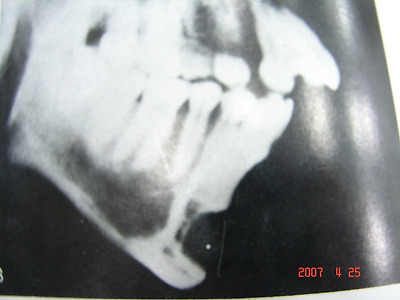

실리콘 사용하여 무턱을 교정한 환자 엑스레이, 수술10년째 환자는 아래 앞치아의 통증 호소로 엑스레이 확인 결과 실리콘에 눌린 뼈가 녹아서 아래치아 뿌리(치근)신경까지 손상을 보인 실리콘 사용한 무턱 수술 10년째 엑스레이.